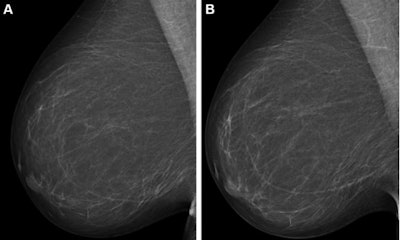

Full-field digital mammograms (right mediolateral oblique view) in a 59-year-old woman show (A) the screening mammogram obtained during the study period and (B) the screening mammogram obtained in the subsequent screening round. The first screening mammogram (A) had a very low combined risk score (lowest 0.1%) as determined by the combination model with texture risk and the examination score. The woman was not recalled and did not receive a breast cancer diagnosis throughout the five-year follow-up. Images and caption courtesy of RSNA.The researchers trained the combination model on mammography exam data taken from 39,345 Dutch women; the researchers also used retrospective data from 119,650 Danish women who underwent consecutive screening mammography between 2012 and 2015 and at least five years of follow-up data.